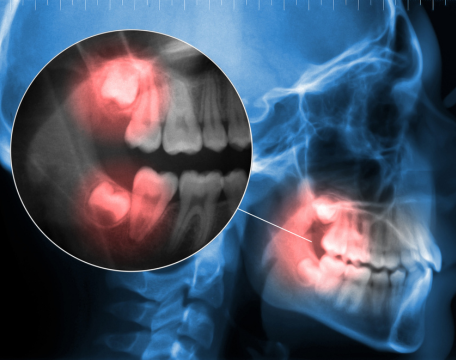

私たちの体は、頭蓋骨、下顎骨、筋肉、そして歯が、絶妙なバランスの上に成り立っています。

このバランスが崩れると、顎の痛み(顎関節症)や歯ぎしりだけでなく、肩こり、頭痛、姿勢の歪みなど、全身に様々な不調が現れることがあります。

そのために、コンピューター顎運動診査器(CADIAX)などの精密な検査機器を用い、患者様お一人おひとりの状態を詳細に分析し、最適な治療計画を立てていきます。